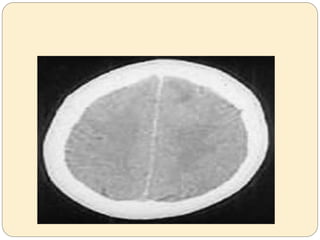

Def: Cerebral edema resulting from urea removal

from the blood more rapidly than from the CSF

and brain tissue generating a urea osmotic

gradient responsible for water moving into brain

cells.

Disequilibrium Syndrome Def: Cerebraledema resulting from urea removal from the blood more rapidly than from the CSF and brain tissue generating a urea osmotic gradient responsible for water moving into brain cells.